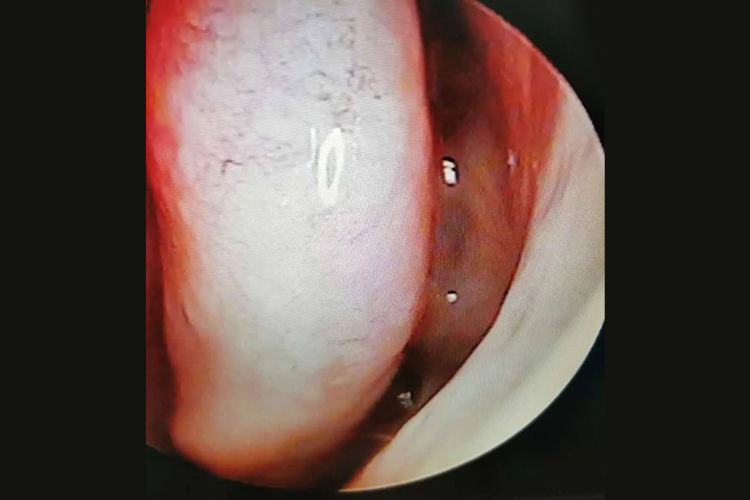

临床以反复鼻痒、喷嚏、鼻塞和水样涕症状为主,在接触变应原后或睡眠时加重,起床及活动后减轻;鼻腔检查时可见鼻甲苍白、水肿,鼻腔有较多稀薄黏液样鼻涕。

疾病无症状期间,鼻黏膜大多为正常,但发病期间患者的鼻黏膜可呈苍白、充血样或淡蓝色,通常为高度水肿,以下鼻甲更为明显。